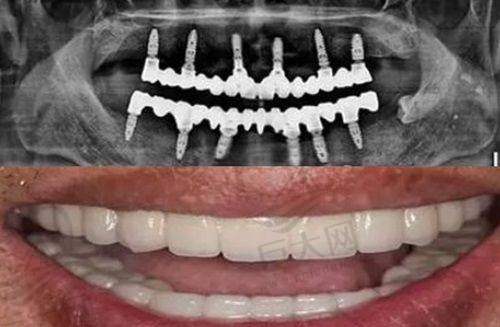

在设备上,拥有韩国奥齿泰3D导航仪,种牙误差小于0.1毫米;iTero口扫仪5分钟出隐形牙套动画,预览不踩雷;还有儿童专属的卡通动画治疗椅。医生团队实力雄厚,种植王峰有原北大口腔种植科10年经验,正畸李萌是隐适美黑钻认证医生,儿科护牙能手张护士是哄娃高手。服务细节到位,全程一对一服务,独立诊室配空气洁净器,候诊有免费咖啡和儿童游乐区,种植牙5年质保,矫正保持器免费换新。再结合前面提到的项目价格优势,整体性价比非常高。